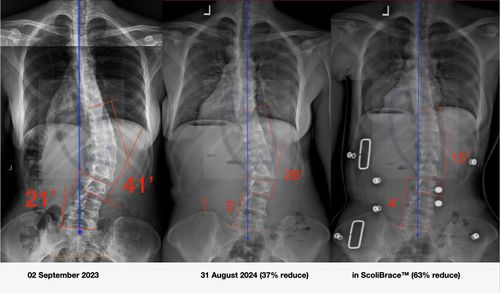

Scoliosis Brace Options Explained: From Traditional Bracing to Advanced 3D Corrective ScoliBrace Technology

Compare scoliosis brace options including Boston, Chêneau, SpineCor, and ScoliBrace. Learn how modern 3D corrective bracing improves alignment, comfort, and treatment outcomes.